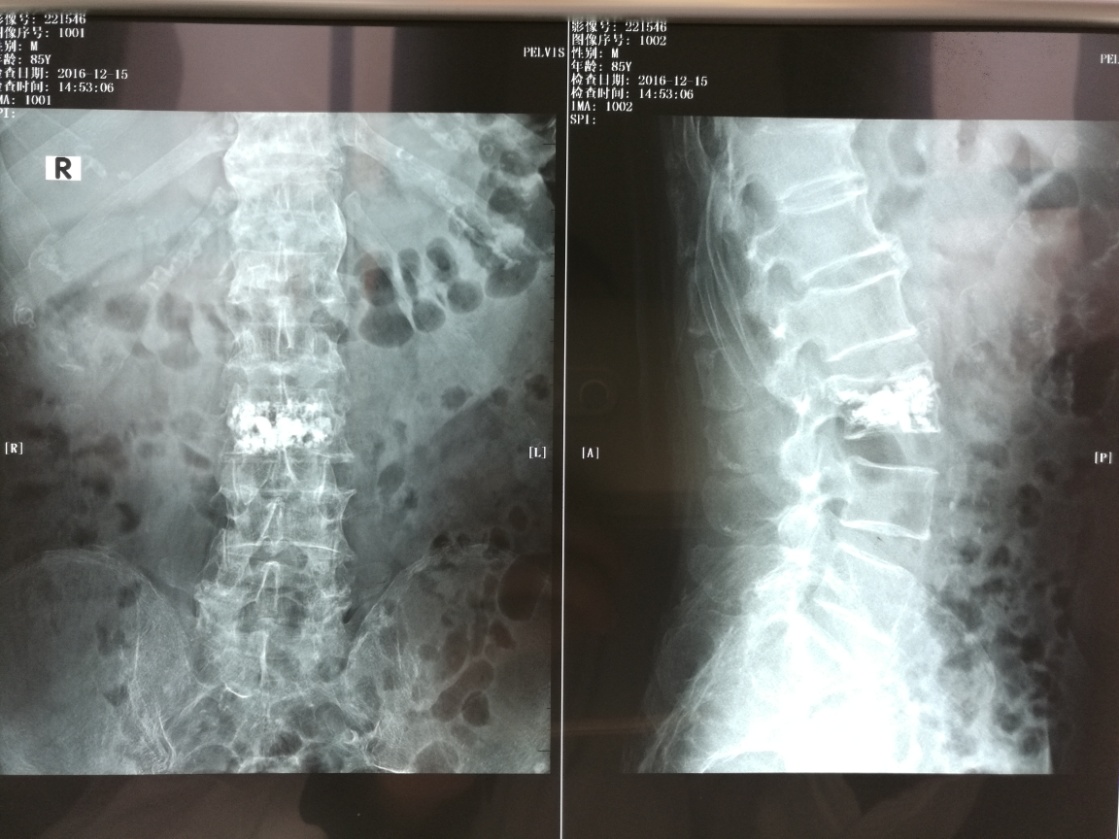

我院骨科于近日成功开阵多例经皮椎体后凸成形术(PKP)及经皮椎体成形术(PVP),数名患者均恢复良好。这是我院骨科在积极开拓新业务,开展新技术,更好地为广大患者服务的又一硕果。

骨质疏松性胸腰椎压缩骨折是中老年人的常见病、多发病。主要表现为负重及动态下的腰背部剧烈疼痛,使患者相当痛苦,生活十分不便。对病人而言,需长期卧床静养,服药保守治疗效果差且缓慢。一些采用开刀的方法进行治疗的老年患者均需要面临极大的手术风险。近期,经我院骨科的努力,成功对数例骨质疏松性胸腰椎压缩骨折患者实施了经皮椎体后凸成形术(PKP)及经皮椎体成形术(PVP)。

经皮椎体后凸成形术(PKP)及经皮椎体成形术(PVP)是一种微创性手术,具有损伤小、术后恢复快、手术外表美观和住院时间短等优点。这类微创手术与传统的开刀手术相比,病人痛苦轻、住院时间短、疼痛症状缓解快,术后12小时即可负重行走,出血少及并发症少,是骨质疏松性胸腰椎压缩骨折患者的首选治疗方案。此次新技术的开展,标志着我院在微创手术方面又迈上了一个新台阶,对骨科微创手术的全面开展起到了积极的推动作用。